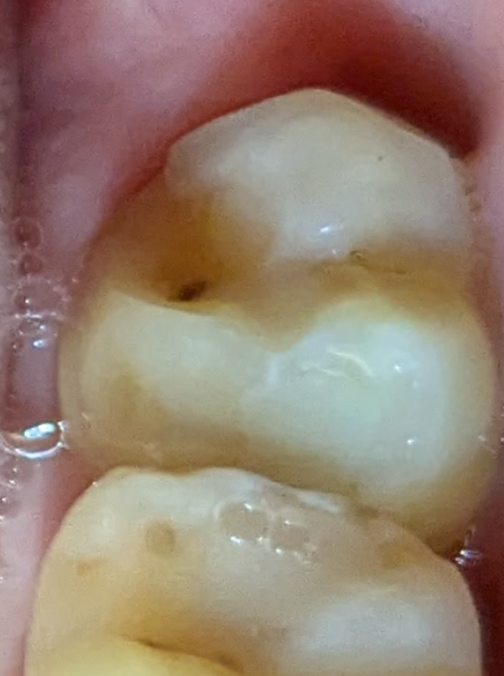

es würde vor 2 Jahren mal eine Aufnahme gemacht, da war der Punkt glaube ich schon da…

könnte es dann einen “inaktivierte” Karies sein? Sollte man das trotzdem füllen?

füllen nicht notwendig, ist ja vermutlich seit jahren stabil …